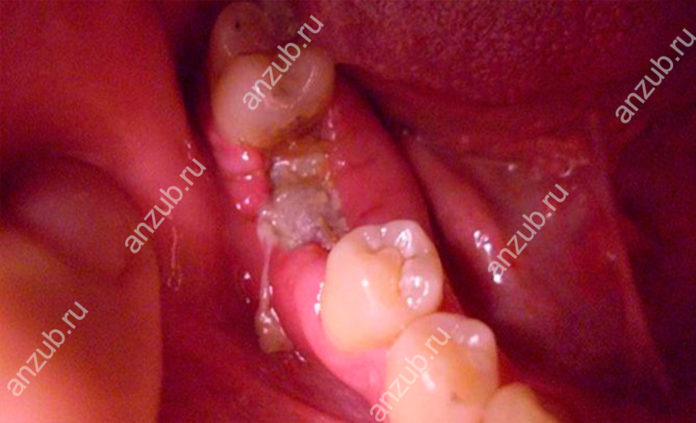

Как узнать, что произошло нагноение

Когда начинает гноиться десна, патологию можно распознать по следующим симптомам:

- мягкие ткани около ранее удаленного зуба, а также над и под ним, краснеют и отекают,

- постепенно в области лунки и рядом расположенных участках нарастает боль: она может быть тянущей или пульсировать,

- из лунки выделяется гной,

- из полости рта неприятно пахнет.

Если своевременно не принять меры, развивается общая слабость, повышается температура, отекает лицо на стороне воспалительного процесса, болевые ощущения принимают агрессивный характер – прием анальгетиков снимает их лишь на короткое время, а их локализация распространяется на голову, ухо, шею, челюсть.